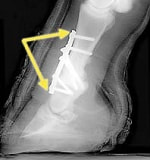

固定術・形成術

関節固定術